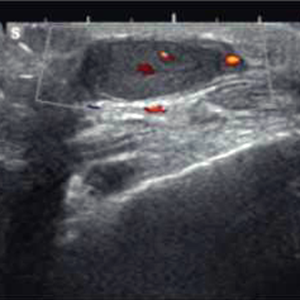

Octubre 2025. Conci Carpinella

Femenina 59 años. Asintomática, Hallazgo en control anual.